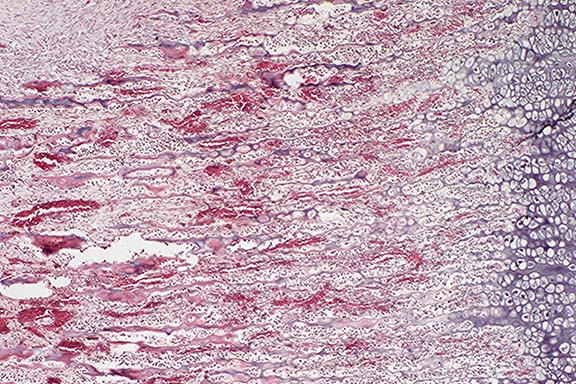

Case 19-3. Bone. Demonstrates moderately differentiated chondroid cells producing a basophilic chondroid matrix. 20X

AFIP Diagnosis: Tibial tarsal bone: Chondrosarcoma, Chesapeake Bay Retriever, canine.

Conference Note: Chondrosarcoma (CS) is the second most common skeletal neoplasm in dogs and man.1 As with osteosarcoma (OS), CS most frequently affects large breed dogs. However, in contrast to OS, CS rarely affects the giant breeds such as the Great Dane or St. Bernard.

Primary chondrosarcomas arise from existing normal cartilage and from perichondrium. Secondary chondrosarcomas develop from abnormal cartilage, such as that which exists in osteochondromas. Chondrosarcomas are usually found in mature animals, and occur more often in the pelvis, nasal cavity, sternum, and ribs than in the axial skeleton.5 In contrast with OS, CS grow more slowly and metastasize later. They may be associated with recurrences many years after initial surgery.1 A recent report by Hahn et al. described bilateral renal metastases of a nasal chondrosarcoma in a dog, which occurred one year following nasal surgery and radiotherapy for the primary tumor.6